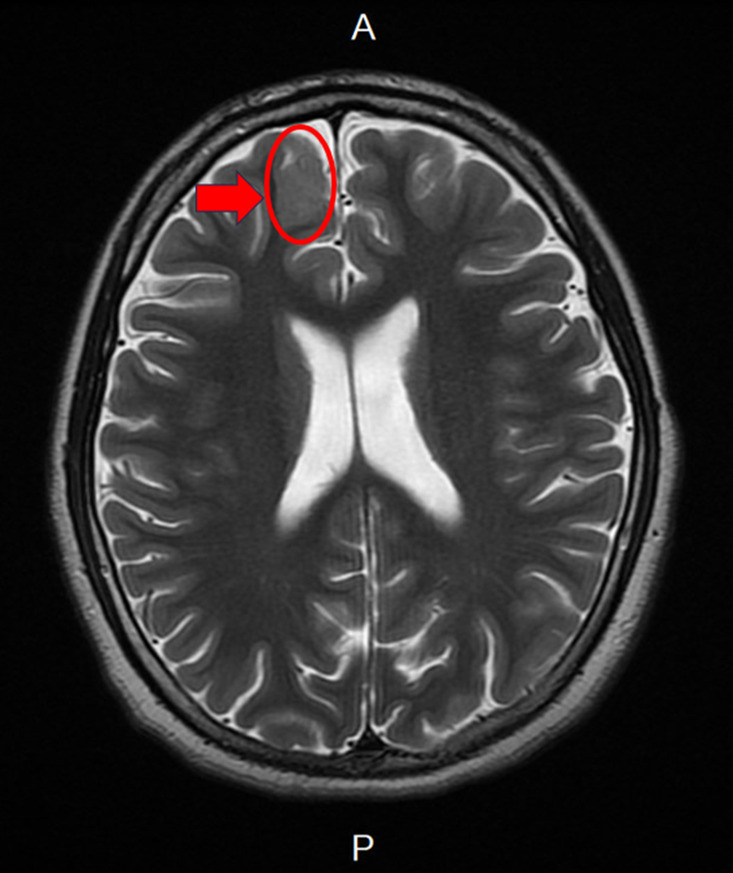

14歲少年癲癇規律服藥仍頻繁發作 疑腦皮質發育不良

14歲自閉症男孩3歲起因癲癇在外院接受抗癲癇藥物治療,但仍頻繁發作,且意識喪失以及嚴重學習障礙,因癲癇控制不佳,轉至新竹臺大分院就醫,小兒部醫師張寶玲評估發現,男孩腦波檢...…